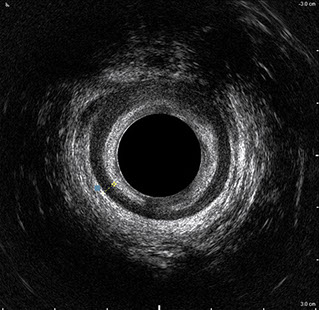

L’ecografia transanale è un esame diagnostico per immagini che consiste nell’introduzione di un trasduttore ad ultrasuoni. Le immagini qualitativamente migliori del canale anale sono ottenute usando un trasduttore rotante, montato in un manipolo rigido, che fornisce un’immagine a 360°. Con le apparecchiature più moderne è anche possibile ottenere immagini tridimensionali.

L’ecografia transanale permette di distinguere la sottomucosa che riveste il canale anale, lo sfintere anale interno, e lo sfintere anale esterno.

Proctal dispone di apparecchiatura per ecografia endoanale 3D con sonda rotante.